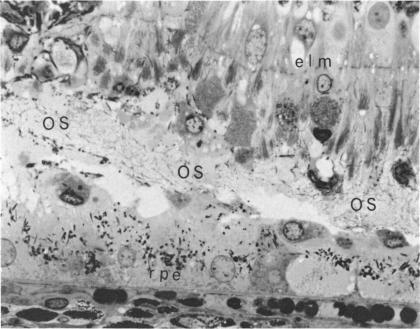

Systemic immunization with purified homologous rhodopsin from retinal outer segments induced blindness in primates (Macaca mulatta). Inflammation and characteristic retinal changes were the earliest clinical signs of the disease. Perivasculitis, subretinal exudations and bullous detachments of the retina were progressive and unrelenting pathological processes leading to rapid and irreversible visual deterioration. Electroretinographic responses (ERG) at this stage of the disorder became abolished. Antibodies and delayed hypersensitivity to rhodopsin were demonstrated only in the experimental diseased animals. Homologous visual purple appears to be organ and immunopathologically specific. Histological confirmation of these findings showed a pathological spectrum of destructive alterations confirmed specifically to the outer segments of the entire retina. The pathologic reaction was supported by a distinct and pronounced granulomatous inflammatory response.